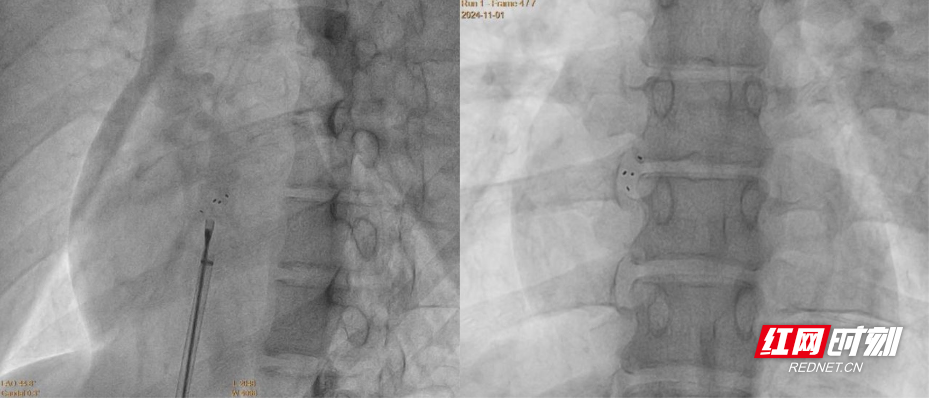

手术在局部麻醉下进行,术中同步运用DSA与超声双重影像引导。团队凭借丰富经验,精准释放封堵器,术后超声提示封堵器位置良好,无残余分流。